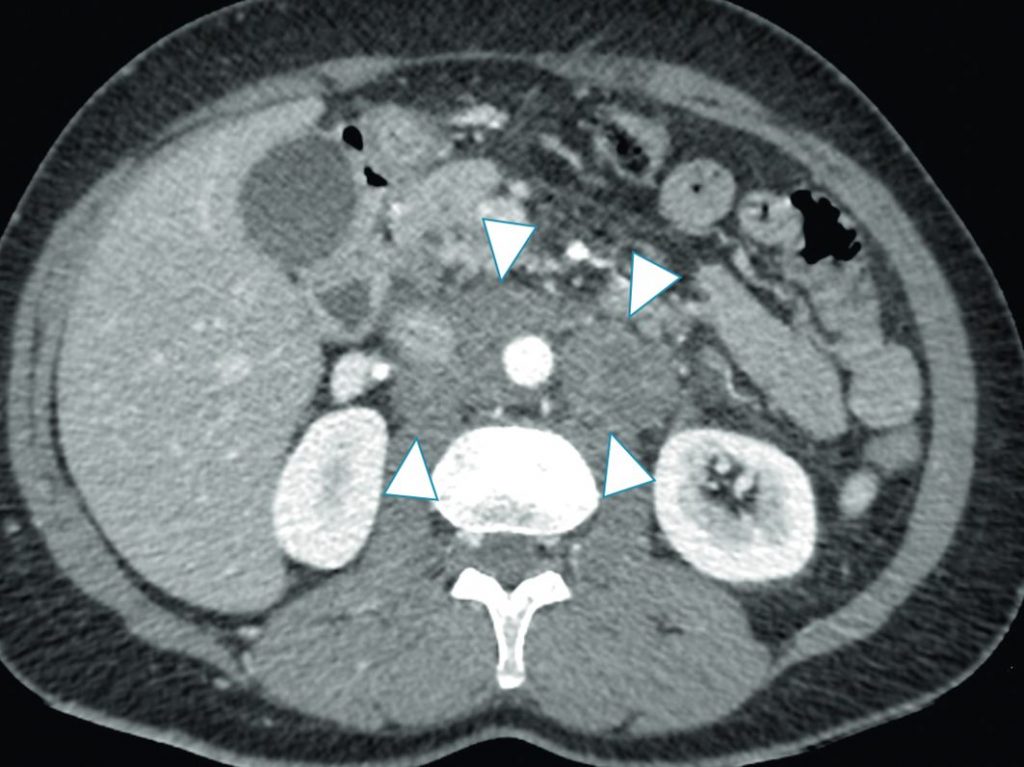

Le scanner thoraco-abdomino-pelvien recherche en particulier des métastases pulmonaires et des adénopathies. Ces dernières se traduisent par une ou plusieurs masses ganglionnaires le plus souvent homogènes (de plus de 1 cm de petit axe) autour des gros vaisseaux rétropéritonéaux, premiers relais ganglionnaires (figure 32.2).

Fig. 32.2 TDM après injection de produit de contraste iodé : multiples adénopathies rétropéritonéales (têtes de flèches).

Source : CERF, CNEBMN, 2022.